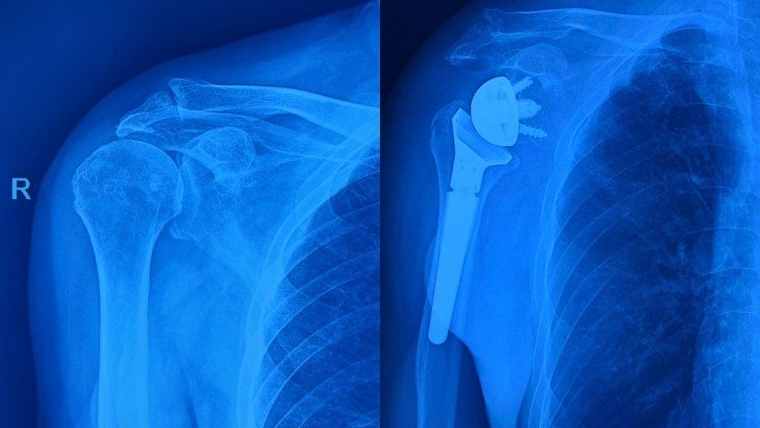

Thay khớp vai là quá trình thay thế toàn bộ hoặc một phần của khớp vai bằng khớp nhân tạo. Phẫu thuật thay khớp vai được phân loại như sau:

Phẫu thuật thay khớp vai nhân tạo đảo ngược: Là một loại phẫu thuật thay khớp vai đặc biệt, trong đó cấu trúc tự nhiên của khớp vai bị thay đổi theo cách ngược lại để cải thiện chức năng và giảm đau. Cụ thể, đầu xương cánh tay được biến đổi thành ổ chảo, ổ chảo xương bả vai được biến đổi thành chỏm hình cầu. Bằng cách thay đổi cấu trúc này, phẫu thuật thay khớp vai nhân tạo đảo ngược sẽ không phụ thuộc nhiều vào các gân cơ chóp xoay để duy trì sự ổn định và chức năng của khớp, do đó giúp hạn chế sự tổn thương đến các gân cơ chóp xoay.

Bác sĩ phẫu thuật thay khớp vai bằng cách cắt bao khớp, cho phép nhìn thấy khớp vai. Phần chỏm xương cánh tay được loại bỏ bằng một cái cưa xương. Sau đó, bác sĩ làm rỗng lòng tủy xương cánh tay để chọn kích thước thích hợp của dụng cụ nhân tạo, rồi đặt dụng cụ đó vào xương cánh tay. Tiếp theo, phần sụn hư của ổ chảo được cắt bỏ và tiến hành đục lỗ để đặt ổ chảo nhân tạo.

Cuối cùng, các bộ phận nhân tạo của xương cánh tay và ổ chảo được đặt vào vị trí và chỏm khớp được nối lại. Bác sĩ phẫu thuật kiểm tra độ khít của khớp. Khi đã hài lòng với độ vừa vặn, bao khớp được khâu lại. Các cơ được đưa về vị trí ban đầu và da cũng được khâu lại.